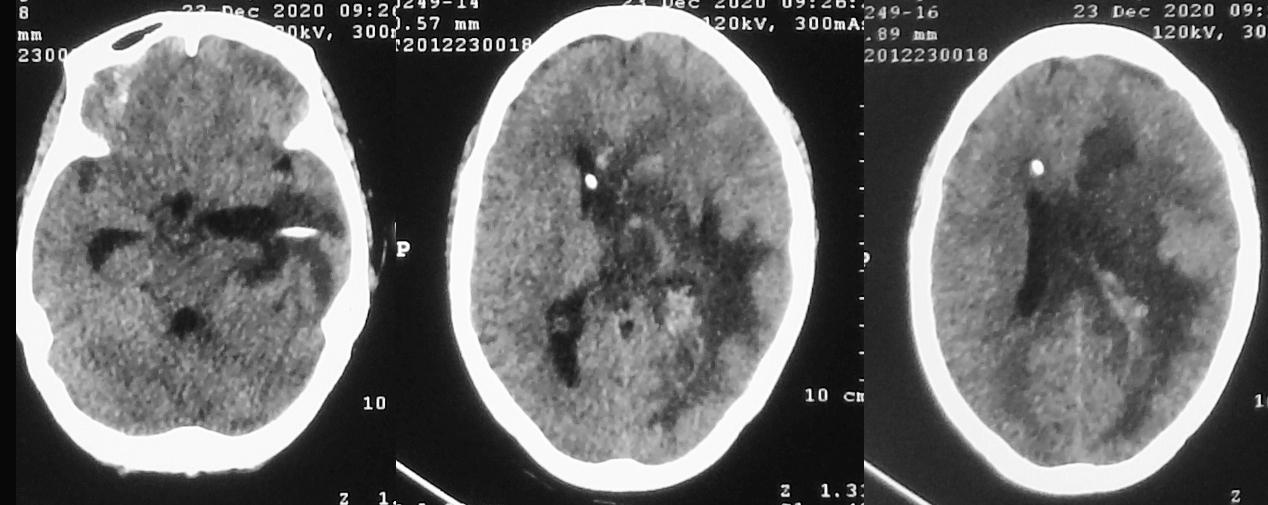

脑脓肿清除术后第15天,左侧颞角外引流术后第14天,右侧脑室穿刺术后12天,即2020年12月23日,复查头颅CT见术区脑水肿较前(2020年12月16日)减轻( 图-17 )。

图-17: 2020年12月23日头CT

2020年12月24日再次复查头颅CT较前无明显变化( 图-18 )。

图-18: 2020年12月24日头CT